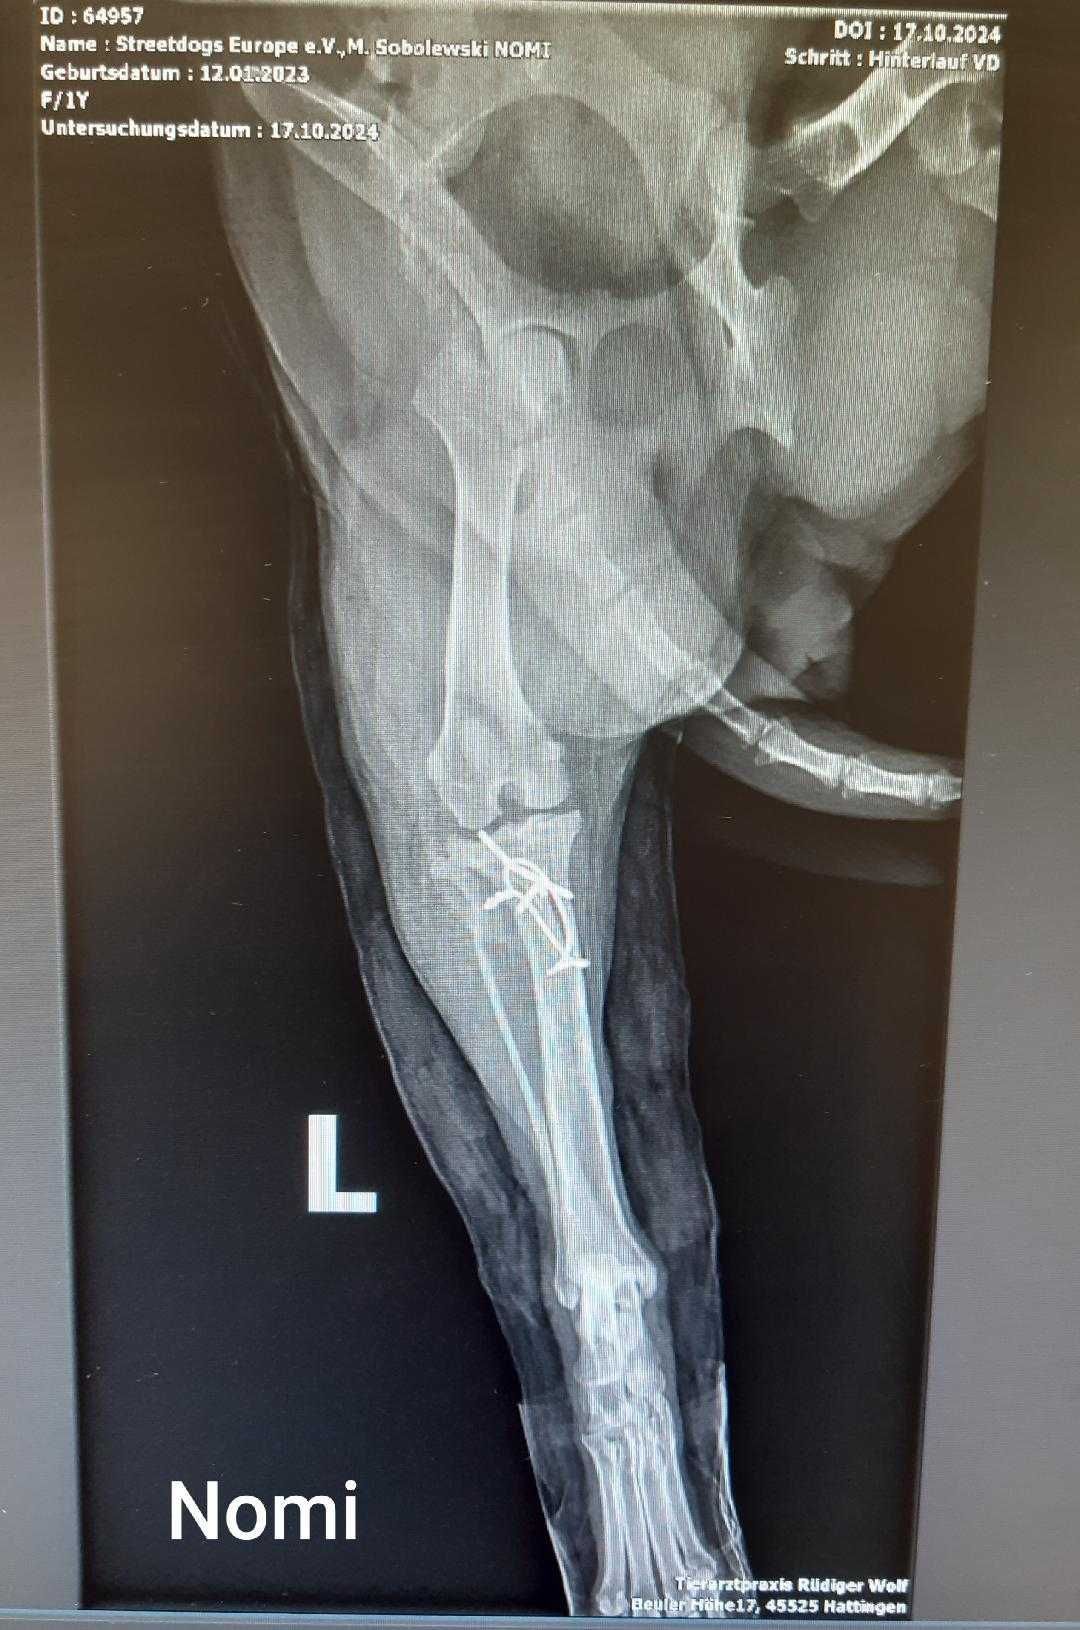

Das tat echt weh und ich habe mein Bein sicherheitshalber erst mal krumm zur Seite gestreckt… und auftreten konnte ich auch nicht mehr! Annette und Stefan waren total erschrocken und wir sind noch ganz schnell zum Doc nach Hattingen gefahren. Da wurde mein Bein wieder fotografiert - wie ihr auf dem Bild sehen könnt, sitzt noch alles dort wo es hingehört. Es ist nochmal gut gegangen, puh! Da hab ich echt Glück gehabt!!

Hier seht ihr jetzt auch meine Innenfotos - da erkenne ich mich überhaupt nicht. Ich verstehe auch nicht, warum es so interessant ist, sich meine Knochen anzugucken. Aber für euch Menschen scheinen die sehr interessant zu sein.

Vorhin hat mein Pflegefrauchen mit meiner neuen Besitzerin, Annette, telefoniert. Da hab ich mitbekommen, dass mein Knie operiert wurde. Da hat der Doc irgendwas passend gefräst, einen Knochen gekürzt und die Kniescheibe in der richtigen Position befestigt. Morgen ist Kontrolle und da gibt es dann auch die Röntgenbilder.

Ich muss mich wirklich noch ein paar Tage erholen und werde euch daher am Montag berichten wie es mir geht und dann seht ihr auch die Röntgenbilder.